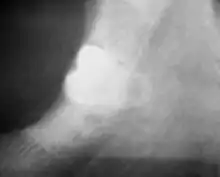

Coronectomy is a procedure where the crown of the impacted wisdom tooth is removed, but the roots are intentionally left in place. It is indicated when there is no disease of the dental pulp or infection around the crown of the tooth, and there is a high risk of inferior alveolar nerve injury.[31]

Coronectomy, while lessening the immediate risk to the inferior alveolar nerve function has its own complication rates and can result in repeated surgeries. Between 2.3% and 38.3% of roots loosen during the procedure and need to be removed and up to 4.9% of cases require reoperation due to persistent pain, root exposure or persistent infection. The roots have also been reported to migrate in 13.2% to 85.9% of cases.[31]